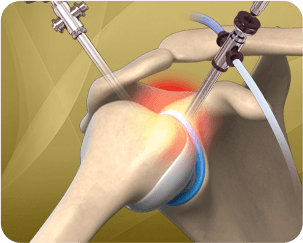

Shoulder replacement surgery is performed to relieve symptoms of severe shoulder pain and disability due to arthritis. The damaged articulating parts of the shoulder joint are removed and socket anatomy of the shoulder joint may be reversed for improved stability when there is accompanying rotator cuff injury. Dr. Liddell performs both Anatomic Shoulder Replacement & Reverse Shoulder Replacement using advanced technology such as 3D computer templating from Biomet Signature for a patient-specific approach.

Know More